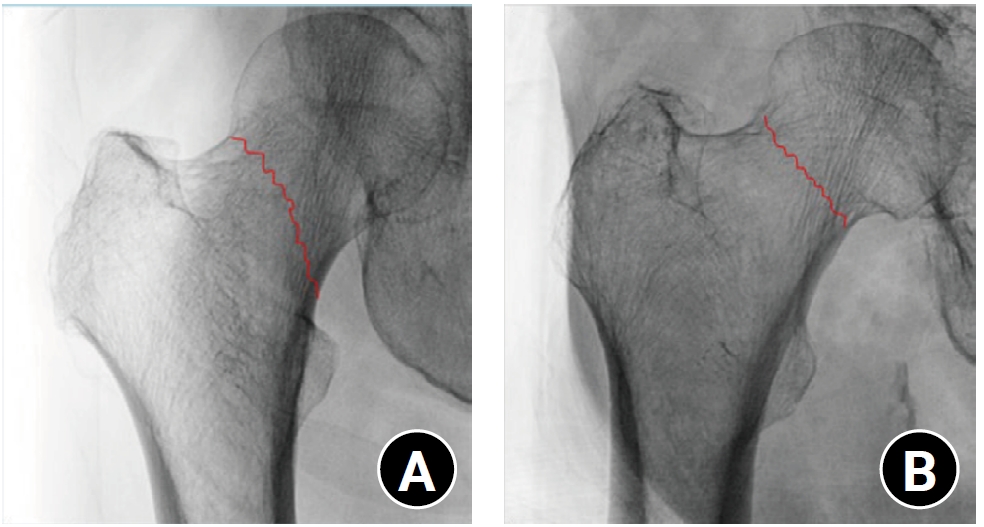

Fractures typically propagate along paths requiring the least energy, often following structural weak points [13-15]. Nalla et al. [14] demonstrated that cracks in the cortical bone propagate along osteons, which act as structural barriers. Similarly, Taylor et al. [15] reported that in the cancellous bone, microcracks align with the bone’s longitudinal axis, whereas cortical bone cracks encountering barriers such as osteons change direction. In the proximal femur, the PCT likely acts as a similar mechanical barrier, redistributing the stress to guide fracture propagation. Our findings support this mechanism. When BMD is high, preserved PCT guide fracture lines vertically, leading to steeper Pauwels angles. As osteoporosis progresses, PCT are lost and these barriers weaken. This is consistent with the decreased Pauwels angles observed in patients with low BMD (Fig. 5).

Relationship between the Pauwels angle and bone mineral density (BMD). (A) Radiograph of a female patient with relatively high BMD (T-score, −1.5). The preserved primary compression trabeculae (PCTs) are associated with a vertically oriented fracture line, resulting in a steeper Pauwels angle. (B) Radiograph of a female patient with low BMD due to advanced osteoporosis (T-score, −4.5). Loss of PCTs leads to a more horizontally oriented fracture line and a decreased Pauwels angle.

Fig. 5. Relationship between the Pauwels angle and bone mineral density (BMD). (A) Radiograph of a female patient with relatively high BMD (T-score, −1.5). The preserved primary compression trabeculae (PCTs) are associated with a vertically oriented fracture line, resulting in a steeper Pauwels angle. (B) Radiograph of a female patient with low BMD due to advanced osteoporosis (T-score, −4.5). Loss of PCTs leads to a more horizontally oriented fracture line and a decreased Pauwels angle.